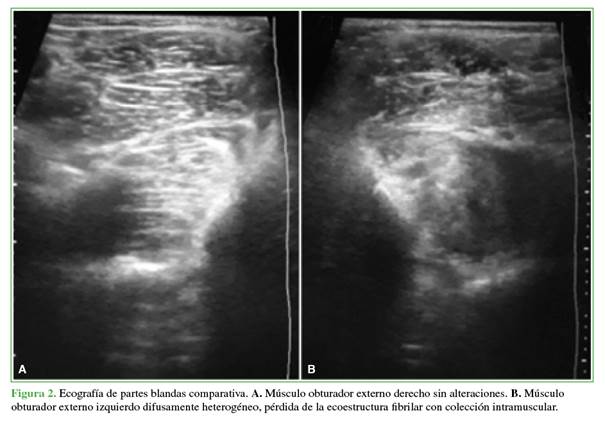

Se procedió a realizar una ecografía y una tomografía computarizada para localizar un foco infeccioso pélvico, que se identificó en el músculo obturador interno. Se observó una lesión abscedada que se podía drenar (Figura 2). No contamos con la posibilidad de realizar una resonancia magnética inicial, ya que, en nuestro medio, no es posible emplearla de forma temprana.